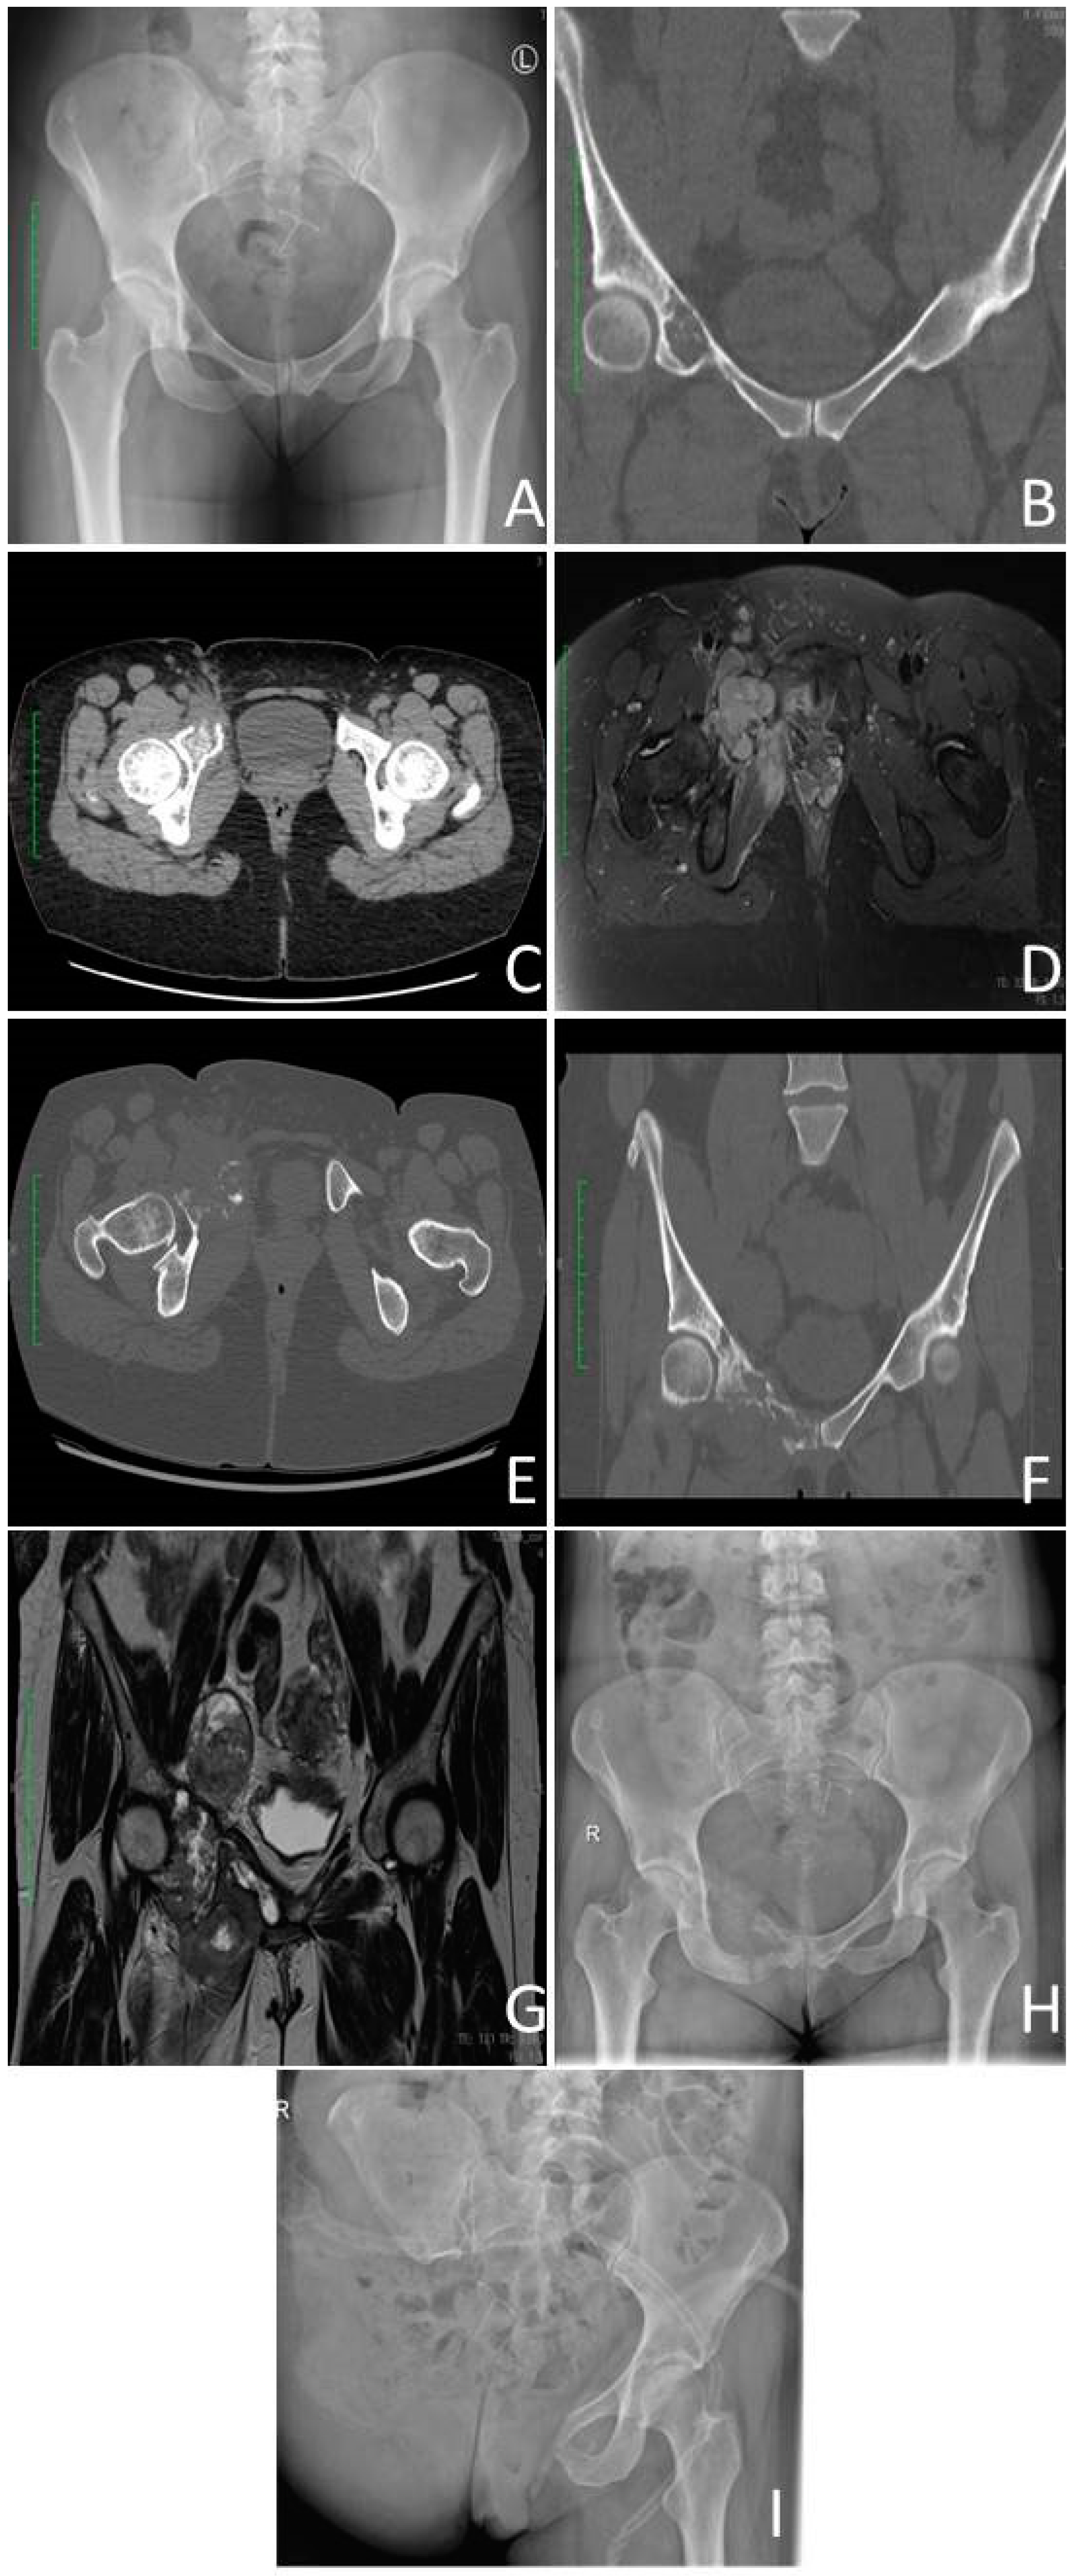

3.4.1. Radiological Criterium

- Littrell, L.A.; Wenger, D.E.; Wold, L.E.; Bertoni, F.; Unni, K.K.; White, L.M.; Kandel, R.; Sundaram, M. Radiographic, CT, and MR Imaging Features of Dedifferentiated Chondrosarcomas: A Retrospective Review of 174 De Novo Cases. RadioGraphics 2004, 24, 1397–1409. [Google Scholar] [CrossRef]

- Kim, J.-H.; Lee, S.K. Classification of Chondrosarcoma: From Characteristic to Challenging Imaging Findings. Cancers 2023, 15, 1703. [Google Scholar] [CrossRef]

- MacSweeney, F.; Darby, A.; Saifuddin, A. Dedifferentiated chondrosarcoma of the appendicular skeleton: MRI-pathological correlation. Skelet. Radiol. 2003, 32, 671–678. [Google Scholar] [CrossRef] [PubMed]